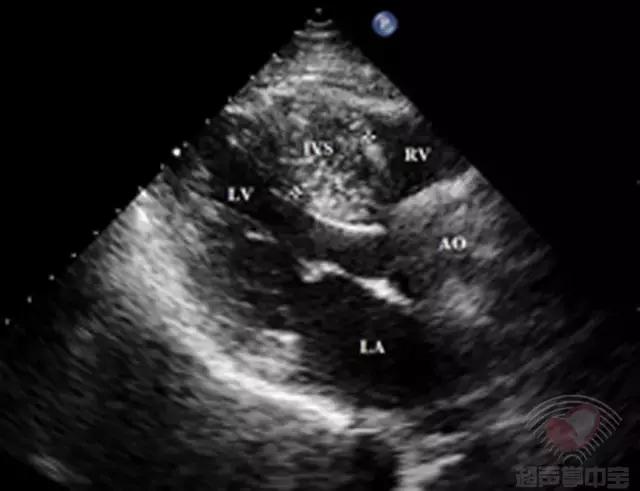

二维超声心动图胸骨旁左室长轴切面可见左室壁非对称性肥厚,室间隔肥厚为主(图1)。基底段厚约20mm,中间段20mm,左室侧壁基底段厚13.1mm,后壁厚11.3 mm,左室心尖厚13mm,心肌回声不均匀,运动幅度尚可,活动僵硬。

图1非对称性肥厚型梗阻性心肌病:胸骨旁左室长轴切面示室间隔显著增厚,厚度20mm